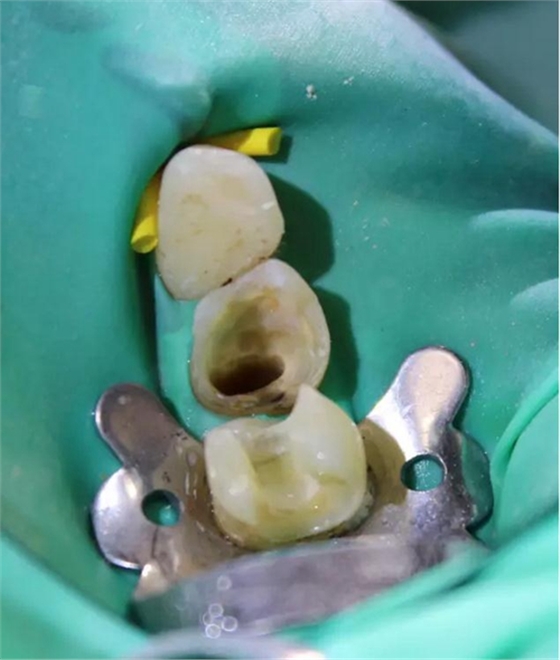

圖4 該病例中,左下4根充失敗,左下5牙髓壞死。兩個牙齒均需要根管治療和修復(fù)。

圖5 根管治療術(shù)后。左下4需要使用纖維樁,并用雙固化樹脂粘結(jié)劑粘結(jié)。左下5無需纖維樁。但2個牙齒均需要進(jìn)行覆蓋牙尖的修復(fù)。